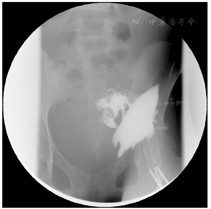

针对存在CD外科并发症(腹腔感染,肠梗阻)及营养不良的患者,需积极诱导疾病缓解,纠正营养不良,控制感染,为手术创造条件。治疗措施:(1)营养支持:患者存在肠梗阻、肠瘘及腹腔感染,缺乏有效的肠内营养通路,行肠外营养的同时积极尝试肠内营养,间接能量测定REE为876 kcal/d,实际能量需求为(1.2-1.5)×REE=1 051-1 314 kcal/d。通过放置肠梗阻导管建立有效的肠内营养通道(图3)。(2)控制腹腔感染:左下腹瘘口处置入黎氏双套管持续冲洗引流(图4)。

术后行鼻饲肠内营养支持及肠液回输,经降结肠造口排便,患者恢复良好。术后第19天突发全腹部剧痛,并出现血压下降,最低60/30 mmHg(1 mmHg=0.133 kPa),血红蛋白从102 g/L降至48 g/L,凝血功能PT、APTT、PLT、INR、FIB均未见明显异常。腹部CT检查:腹腔肠襻间多发包裹性积液、积血,部分肠管增厚、水肿;DSA血管造影检查:腹腔动脉、肠系膜上动脉、肠系膜下动脉及左侧髂总动脉造影未见出血。考虑患者出现腹腔大出血致失血性休克,出血原因可能如下:(1)知名动脉破裂出血:多起病急,发展快,但患者DSA检查已排除知名动脉出血;(2)静脉出血:血肿多聚集于出血部位,此患者表现为腹腔弥漫积血;(3)毛细血管广泛渗血:术后患者腹腔炎症消退,腹腔压力下降,毛细血管破裂出血,因此,暂不考虑剖腹手术,积极给予输血、补液、抗感染等治疗,患者血压逐渐回升,病情趋于稳定,待血肿液化后行CT引导下多部位腹腔穿刺置管引流(图7),引出积血约2 000 ml。